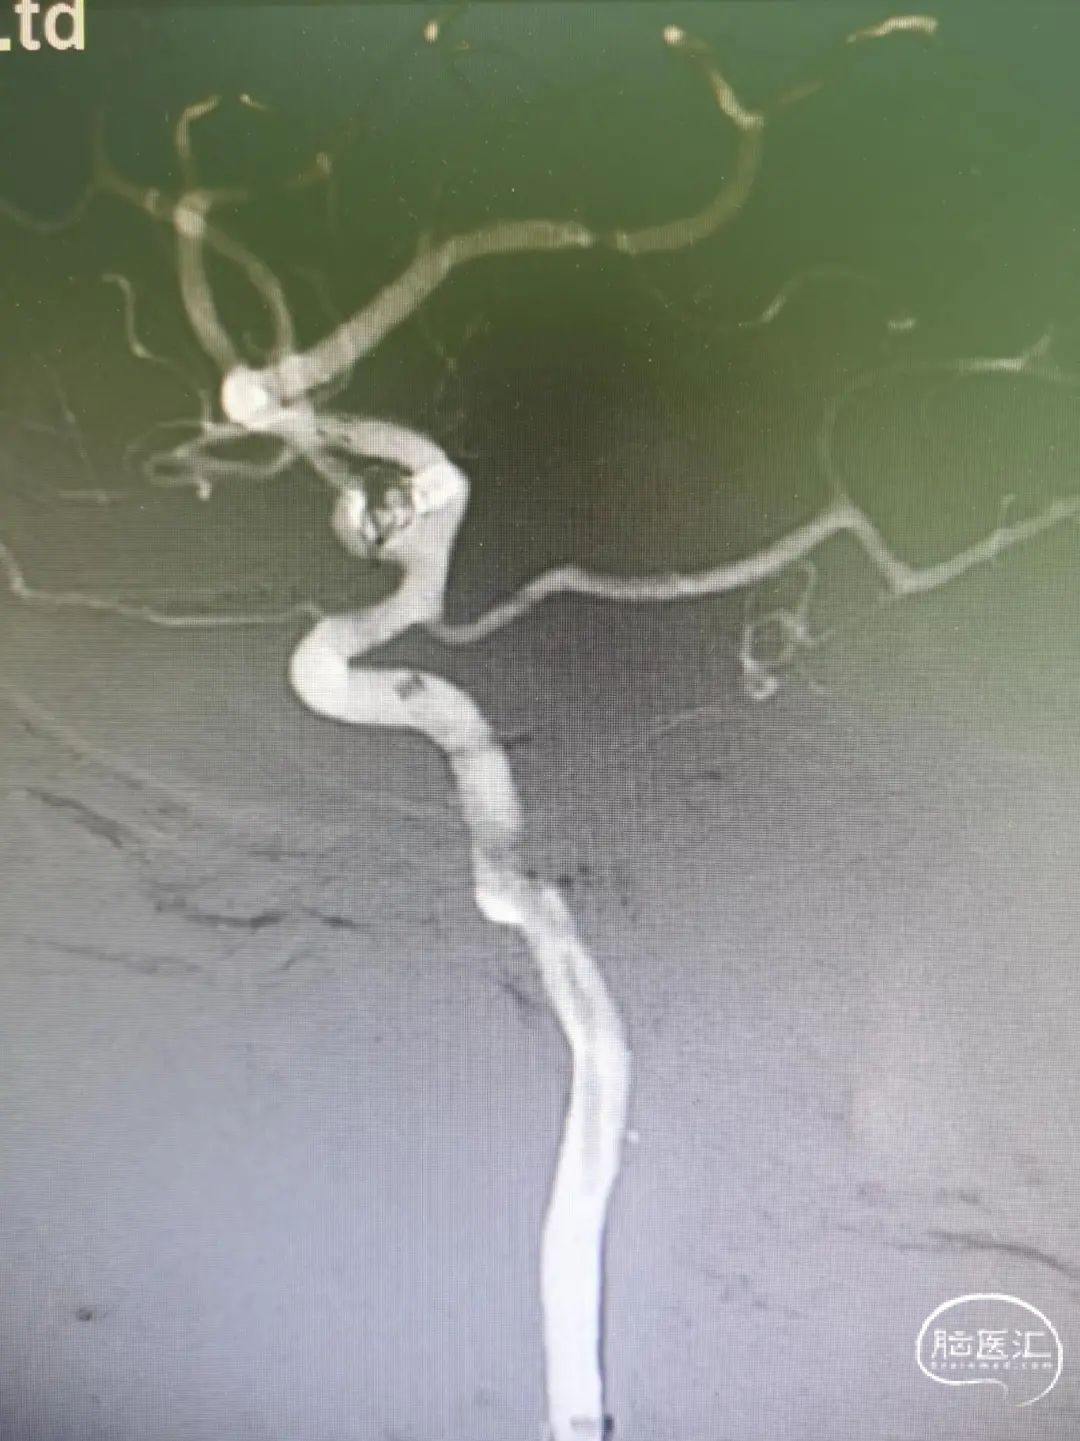

术后即刻工作位造影显示,支架全程打开形态良好,充分贴壁。

术后即刻正/侧位造影显示:各分支血管血流通畅,无出血情况,瘤体内无造影剂充盈。

术后3D造影:支架打开充分,全程贴壁,各分支血管血流通畅,可看到内翻的Mark点也被Evolve贴到了血管壁上,充分体现了Evolve足够强的径向力,预示着Evolve对动脉瘤合并狭窄应用或许是一个不错的选择。